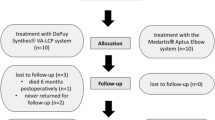

Fourteen fresh frozen, age- and gender-matched cadaveric elbows were 3D-navigated osteotomized simulating a Dubberley type IIB fracture. Specimens were randomized into one of two treatment groups and stabilized with an anterior antiglide plate with additional anteroposterior cannulated headless compression screws (group antiGP + HCS) or a posterolateral distal humerus locking plate with lateral extension (group PLP). Cyclic testing was performed with 75 N over 2000 cycles and ultimately until construct failure. Data were analyzed for displacement, construct stiffness, and ultimate load to failure.

A biomechanical study design was established to evaluate the biomechanical stability of two different fracture fixation techniques for complex coronal plane fractures of the capitellum. For the study purposes, 14 fresh-frozen cadaveric hemitorsi (7 left, 7 right) were obtained from Science Care (Phoenix, AZ). The mean age was 78.2 ± 10.4 years at the time of death, and there were six male and eight female donors. As determined by CT-scan, all elbow specimens had intact distal humeri, and further CT-scan evaluation included bone mineral density assessment in a 10 × 10 mm area at the capitellum to ensure comparable bone quality for fracture fixation.

All 14 elbows were randomly assigned to one of two fracture fixation groups by use of a randomization software, allowing seven age- (within 5 years) and gender-matched distal humeri per group to be tested.

Statistical analysis

Normal distribution of data was assessed with the Shapiro–Wilk test. Descriptive data were calculated using mean and standard deviation. The two groups were compared with the student’s t-test. Significance was set as p < 0.05. A sample size calculation was performed according to the study’s data by Elkowitz et al. [8] using G*Power (Heinrich Heine University, Düsseldorf, Germany), resulting in a sample size of six samples per group to achieve a power > 0.8.